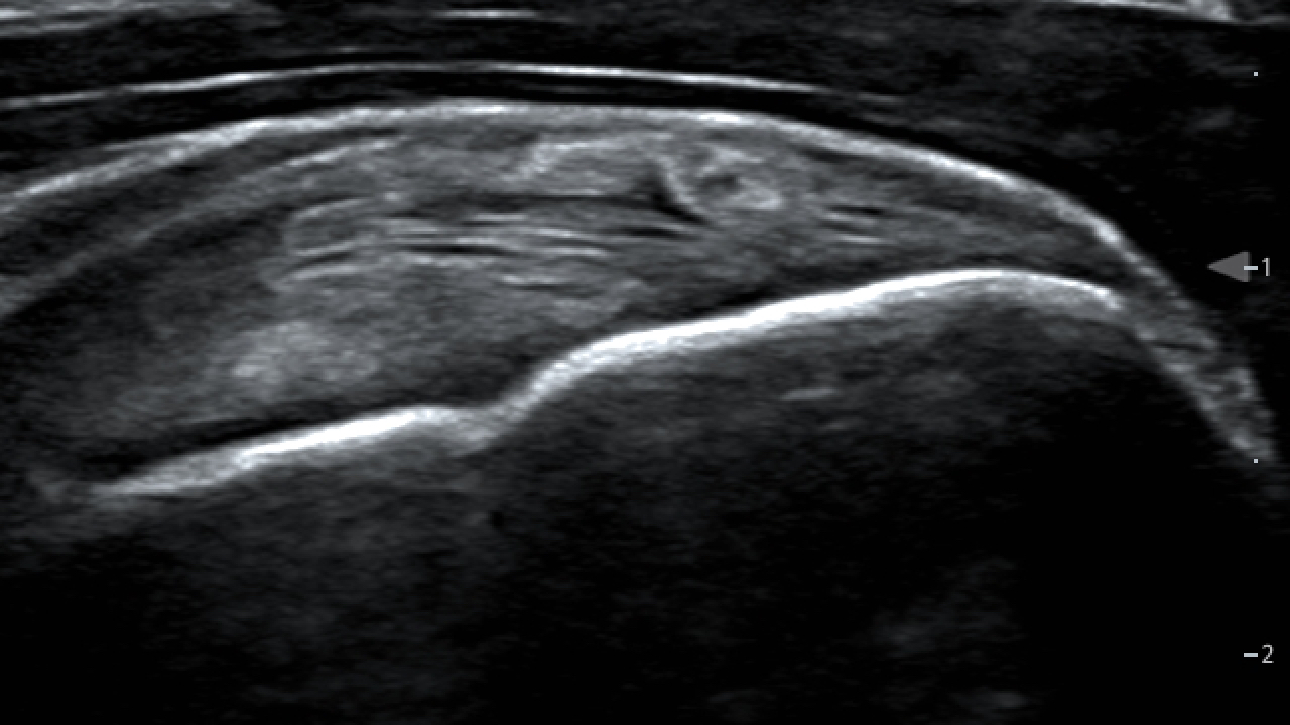

iScanHelper

Dedicated inbuilt tutorial software

- Anatomical diagram illustrations including schematic structure tips and coded tissue

- Standard ultrasonogram comparison with real-time scanning

- Scanning reference picture demonstrating adequate patient position and probe placement tips on scanning skills and diagnosis information